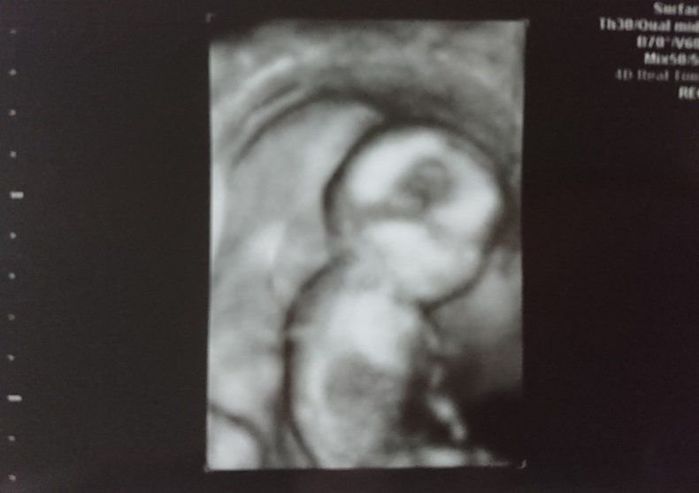

妊娠7週目のエコー写真 赤ちゃんの心臓の鼓動が聞こえた!

年を越して、約2週間ぶりに健診に行きましたが、とても待ち遠しかったです。

前回はエコー画像だけだったので、実感はあまりありませんでしたが、今回は赤ちゃんの心臓の鼓動を聞く事ができたので、とても感動しました。まだ赤ちゃんの袋の大きさは“小豆粒”くらいだそうですが、立派に生きている鼓動が聞けて嬉しかったです。母子手帳をもらいに行きました。